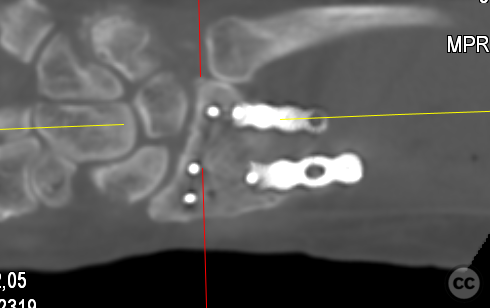

Clinical and radiological findings:  A 72-year-old female sustained a multifragmentary, dorsally displaced distal radius fracture after a fall down stairs. Initial reduction revealed a 180-degree flipped fragment of the volar ulnar articular margin, unreducible by closed means. There was no mention of associated neurovascular compromise or open injury. Radiographs and intraoperative fluoroscopy confirmed the presence of a multifragmentary intra-articular fracture (AO/OTA 23-C3), with a flipped volar ulnar fragment and radial styloid impaction. The distal radioulnar joint alignment was restored postoperatively.

Anatomical surgical approach:  A longitudinal incision was made over the flexor carpi radialis (FCR), zigzagging over the wrist crease. Subcutaneous dissection and incision of the FCR tendon sheath were performed, followed by transection of musculus pronator quadratus fibers along the radial border of the distal FCR. The FCR tendon was retracted ulnarly, and the antebrachial fascia incised. Musculus flexor pollicis longus was identified and retracted ulnarly. The pronator quadratus was incised along its radial border and the watershed line, then elevated subperiosteally to expose the distal radius. Extended distal release of the FCR allowed wide exposure of the ulnar aspect of the lunate facet and volar lip. The flipped volar ulnar fragment was de-rotated and provisionally fixed with a Kirschner wire. Ligamentotaxis for radial styloid reduction was achieved using Kirschner wires in the scaphoid and distal radius, with a wire spreader applied for distraction. Provisional fixation was achieved with multiple Kirschner wires. A mini-fragment T-plate, cut and shaped as a hook plate, was applied to the volar ulnar lip fragment, fixed with bicortical screws, and used to engage dorsal fragments. The radial styloid was addressed with a contoured T-plate, similarly fixed with bicortical locking screws. Final multiplanar fluoroscopy confirmed anatomical reduction and hardware placement.

The flipped volar ulnar articular margin fragment was irreducible by closed means due to capsular attachment and required direct open de-rotation and fixation. The impaction and proximal displacement of the radial styloid fragments were challenging due to persistent traction from musculus brachioradialis and scaphoid pressure; ligamentotaxis using Kirschner wire spreader over the scaphoid facilitated reduction. Fragment-specific fixation was necessary: a custom-shaped hook plate for the volar ulnar lip fragment provided stable fixation and prevented dorsal instability, while a separate T-plate addressed the radial styloid. Bicortical locking screws were used to secure both plates, with some screws engaging dorsal fragments from the volar side. Careful adaptation of pronator quadratus over hardware minimized risk of musculus flexor pollicis longus irritation. Additional suture stabilization of radiocarpal ligaments to pronator quadratus provided secondary ligamnetal support.